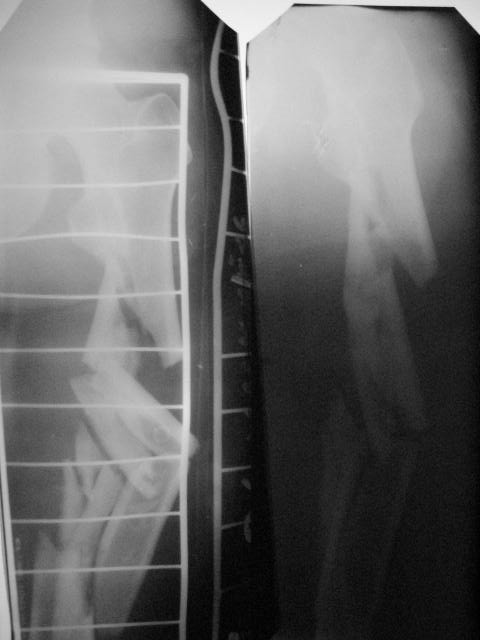

Здравствуйте коллеги! 10.07.2006 года поступил молодой человек 26 лет с Диагнозом:

Открытый (2 В Каплан) многооскольчатый перелом левого бедра. Перелом межмыщелкового возвышения большеберцовой кости без смещения слева. Открытый (1 А Каплан) перелом с/3 -н/3 костей правой голени, перелом пяточной кости справа. На седьмые сутки выполнены операции:1. ЗИМО (статически, Chm-CHARFIX) левого бедра. 2. Остеосинтез стержневым аппаратом костей правой голени и пяточной кости. См. r-gr. На сегодня аппарат демонтирован, больной ходит с ограниченной нагрузкой. Смущает стояние отломков в верхней трети бедра (как то не задумались при планировании операции о реконструктивном или гамме штифте ) хватит ли этих двух винтов для стабильности? С Уважением Владимир Бахарев.